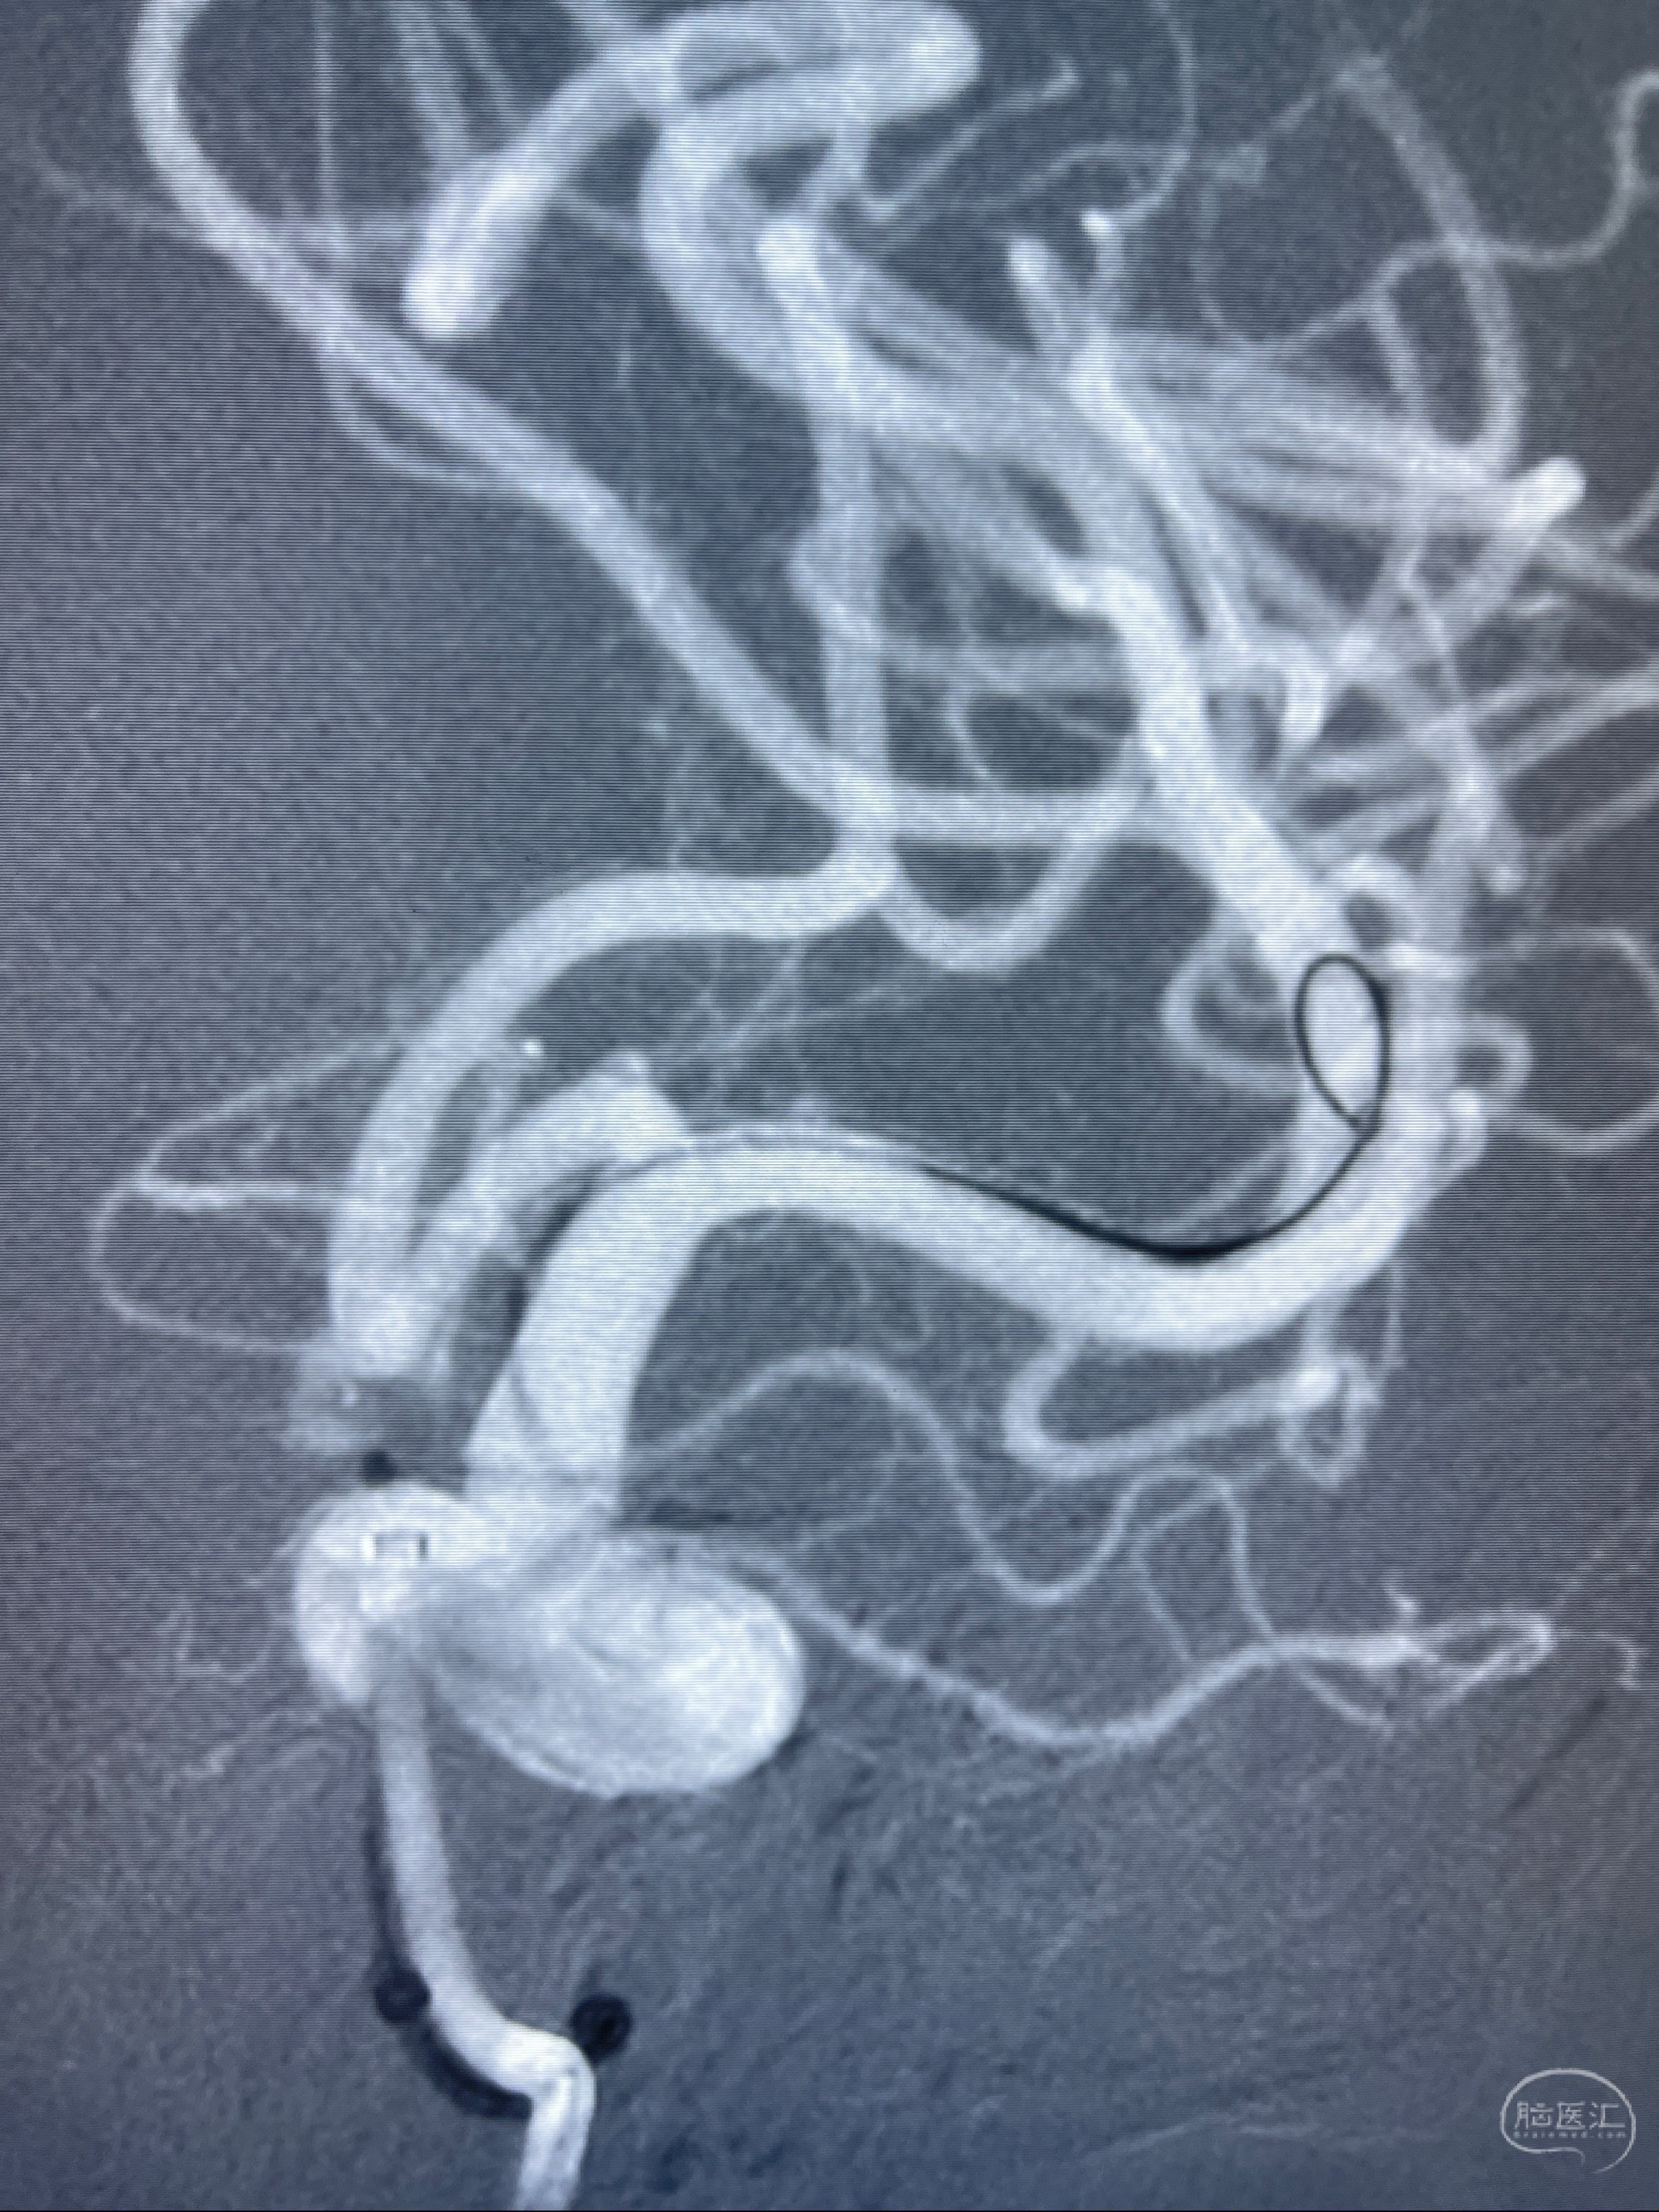

2023-08-01全麻下行双侧颈眼动脉瘤支架辅助栓塞

- pipeling4.5-20mm

- pipeline 4.0-20mm

手术顺利,麻醉苏醒佳,遵嘱动作